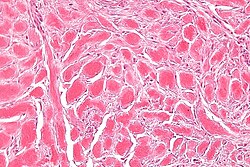

Subdivided into layers:

- Papillary dermis.

- Location: superficial - opposed to the deep aspect of the epidermis.

- Appearance: dense, thick collagen bundles.

- Reticular dermis.

- Location: deep - between papillary dermis and subdermis.

- Appearance: loose connective tissue.